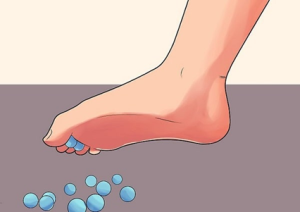

- حرکت بلند کردن مداد

مطابق تصویر شماره ۷ تقویت کف پا و عضلات قوزک پا به حمایت تاندونهای درون تونل تارسال به طور مؤثرتری کمک میکند.

در حالت نشسته یا ایستاده در کنار یک میز، مداد یا تعدادی مهره را روی سطح زمین جلوی خود قرار دهید.

با پای اسیب دیده و با استفاده از انگشتان آنها را بردارید. سپس آن ها را به مدت ده ثانیه در هوا نگه دارید و سپس آن را رها کنید و به حالت اولیه برگردید.

این حرکت را روزانه سه تا پنج بار تکرار کنید.

تصویر شماره ۷، تمرین شماره ۲ : بلند کردن مهره